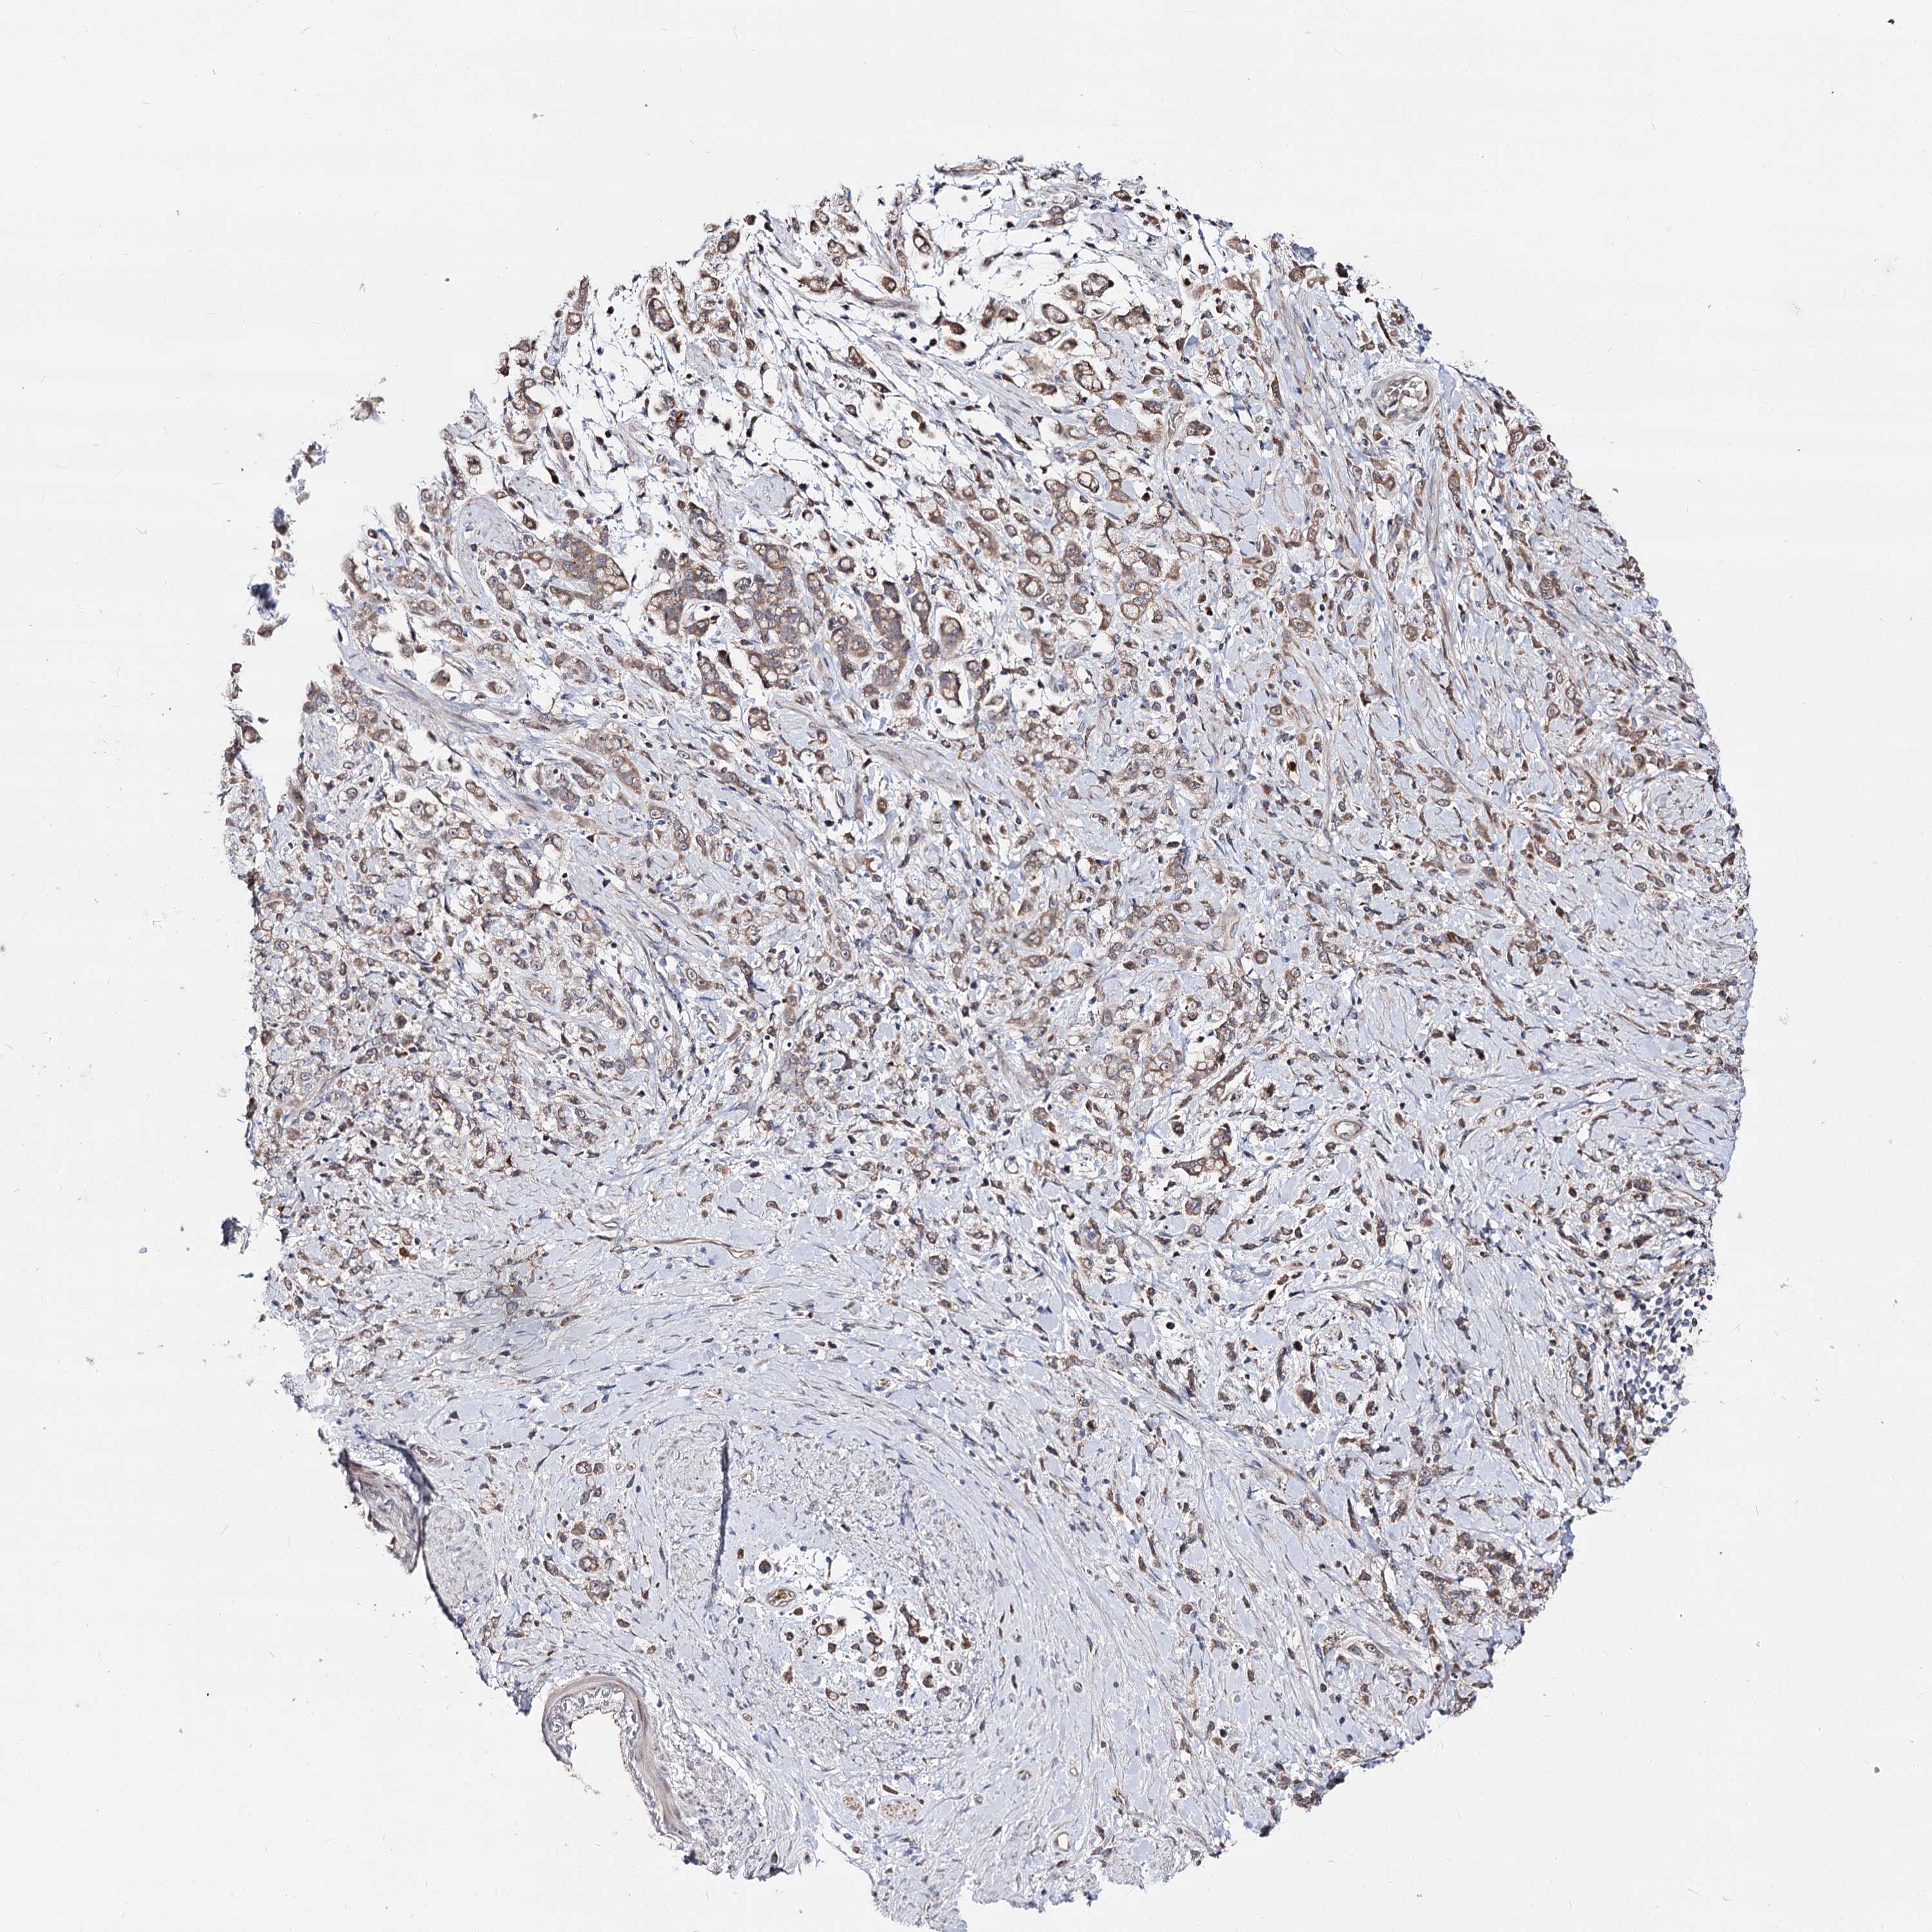

STOMACH CANCER - Protein expressioni

A mouse-over function shows sample information and annotation data. Click on an image to view it in a full screen mode. Samples can be filtered based on level of antibody staining by selecting one or several of the following categories: high, medium, low and not detected. The assay and annotation is described here.

Note that samples used for immunohistochemistry by the Human Protein Atlas do not correspond to samples in the TCGA dataset.

Antibody stainingi

Antibody staining in the annotated cell types in the current human tissue is reported as not detected, low, medium, or high, based on conventional immunohistochemistry profiling in selected tissues. This score is based on the combination of the staining intensity and fraction of stained cells.

Each image is clickable and will lead to virtual microscopy that enables deeper exploration of all samples and also displays staining intensity scores, fraction scores and subcellular localization as well as patient and tissue information for each sample.

Antibody HPA038040

Staining

High

Medium

Low

Not detected

Intensity

Strong

Moderate

Weak

Negative

Quantity

>75%

75%-25%

<25%

None

Location

Nuclear

Cytoplasmic/membranous

Cytoplasmic/membranous,nuclear

Adenocarcinoma, NOS

Adenocarcinoma, High grade